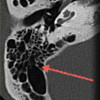

КТ височных костей – метод получения послойных срезов структур пирамиды, барабанной полости и чешуйчатой части височной кости. Исследование выполняется в стандартных проекциях: аксиальной, передней полуаксиальной, передней полукоронарной и коронарной. Компьютерная томография височных костей показано при травматических повреждениях височной области, инфекционных процессах среднего и внутреннего уха, опухолевых поражениях, аномалиях развития, дегенеративных изменениях костных структур, а также в рамках подготовки к кохлеарной имплантации. С целью оценки мягких тканей (мышц, сухожилий, сосудов) используется контрастное усиление. Стоимость томографии варьируется в зависимости от объёма выполненного исследования, использования контраста, квалификации специалиста и характера врачебного заключения (запись результатов на цифровой носитель стоит дороже).

Диагностическую процедуру обычно назначают нейрохирурги, травматологи, челюстно-лицевые хирурги и отоларингологи. С помощью КТ височных костей выявляют переломы, аномалии развития, воспалительные и инфекционные процессы различного генеза и локализации (в области внутреннего и среднего уха, сосцевидного отростка и т. д.). Исследование показано при подозрении на опухоли височных костей. Методика позволяет определить размеры, форму и распространённость новообразования (доброкачественного или злокачественного), выявить наличие метастазов неоплазий другой локализации.

КТ даёт возможность оценить выраженность остеосклероза, подтвердить наличие и выраженность деструкции при распространении гнойных процессов на костные структуры, установить причину выделений из наружного слухового прохода. С помощью КТ височных костей исследуют близлежащие мягкие ткани. Процедуру осуществляют на этапе предоперационной подготовки к установке кохлеарного имплантата.

Томография височных костей занимает от 5 до 30 минут в зависимости от объёма сканирования, при контрастировании продолжительность процедуры увеличивается. Обработка сканов на компьютере дает возможность получить 3D-модель височной области.